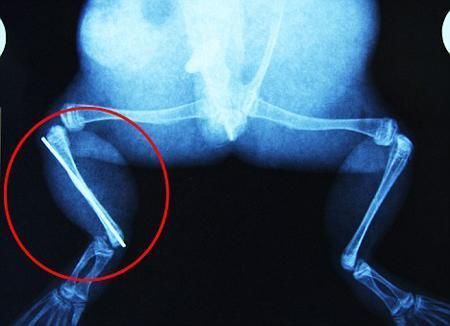

環(huán)球網(wǎng)4月2日報(bào)道 據(jù)《每日郵報(bào)》報(bào)道,上個(gè)月,南非大牛蛙布魯萊的右小腿被鄰居家的一只狗咬到,導(dǎo)致粉碎性骨折,現(xiàn)在經(jīng)過2個(gè)小時(shí)的手術(shù),它的斷腿已經(jīng)被接上,它也因此成為有史以來第一只通過外科手術(shù)用鋼針接上斷腿的青蛙。

野生生物專家安妮經(jīng)常為學(xué)校寫教材,她認(rèn)為這是人類第一次通過手術(shù)給一只青蛙接斷腿。在手術(shù)開始階段,獸醫(yī)把少量給狗用的麻醉藥注入到這只青蛙體內(nèi),讓它失去知覺。然后他在布魯萊的斷腿上切開一個(gè)小口,把一根小鋼針植入腿里。最后獸醫(yī)給它縫了9針,把切口縫合在一起。僅僅幾周后,布魯萊就能在安妮家附近活動(dòng)了。這只青蛙大約已有25歲,主要以嚙齒動(dòng)物、蛇和其他青蛙為食。布魯萊所屬的牛蛙種群正在不斷減小,目前只能在非洲南部的濕地里才能看到這種青蛙。